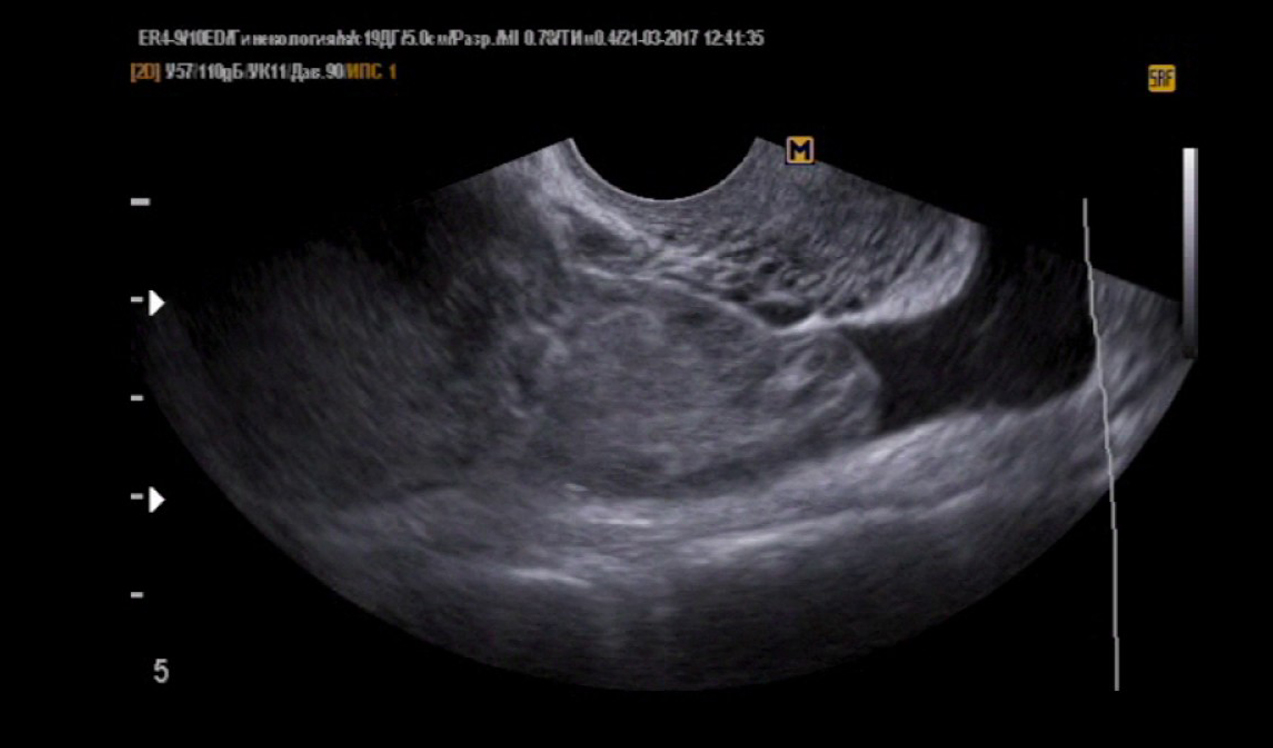

Как выглядит внематочная беременность на узи фото

Фото узи внематочной беременности - Сам себе врач

Внематочная беременность: фото и определение, диагностика на УЗИ на ранних сроках Природа предусмотрела особый орган в организме женщины, где малыш после зачатия растет и развивается - матку . По . . .